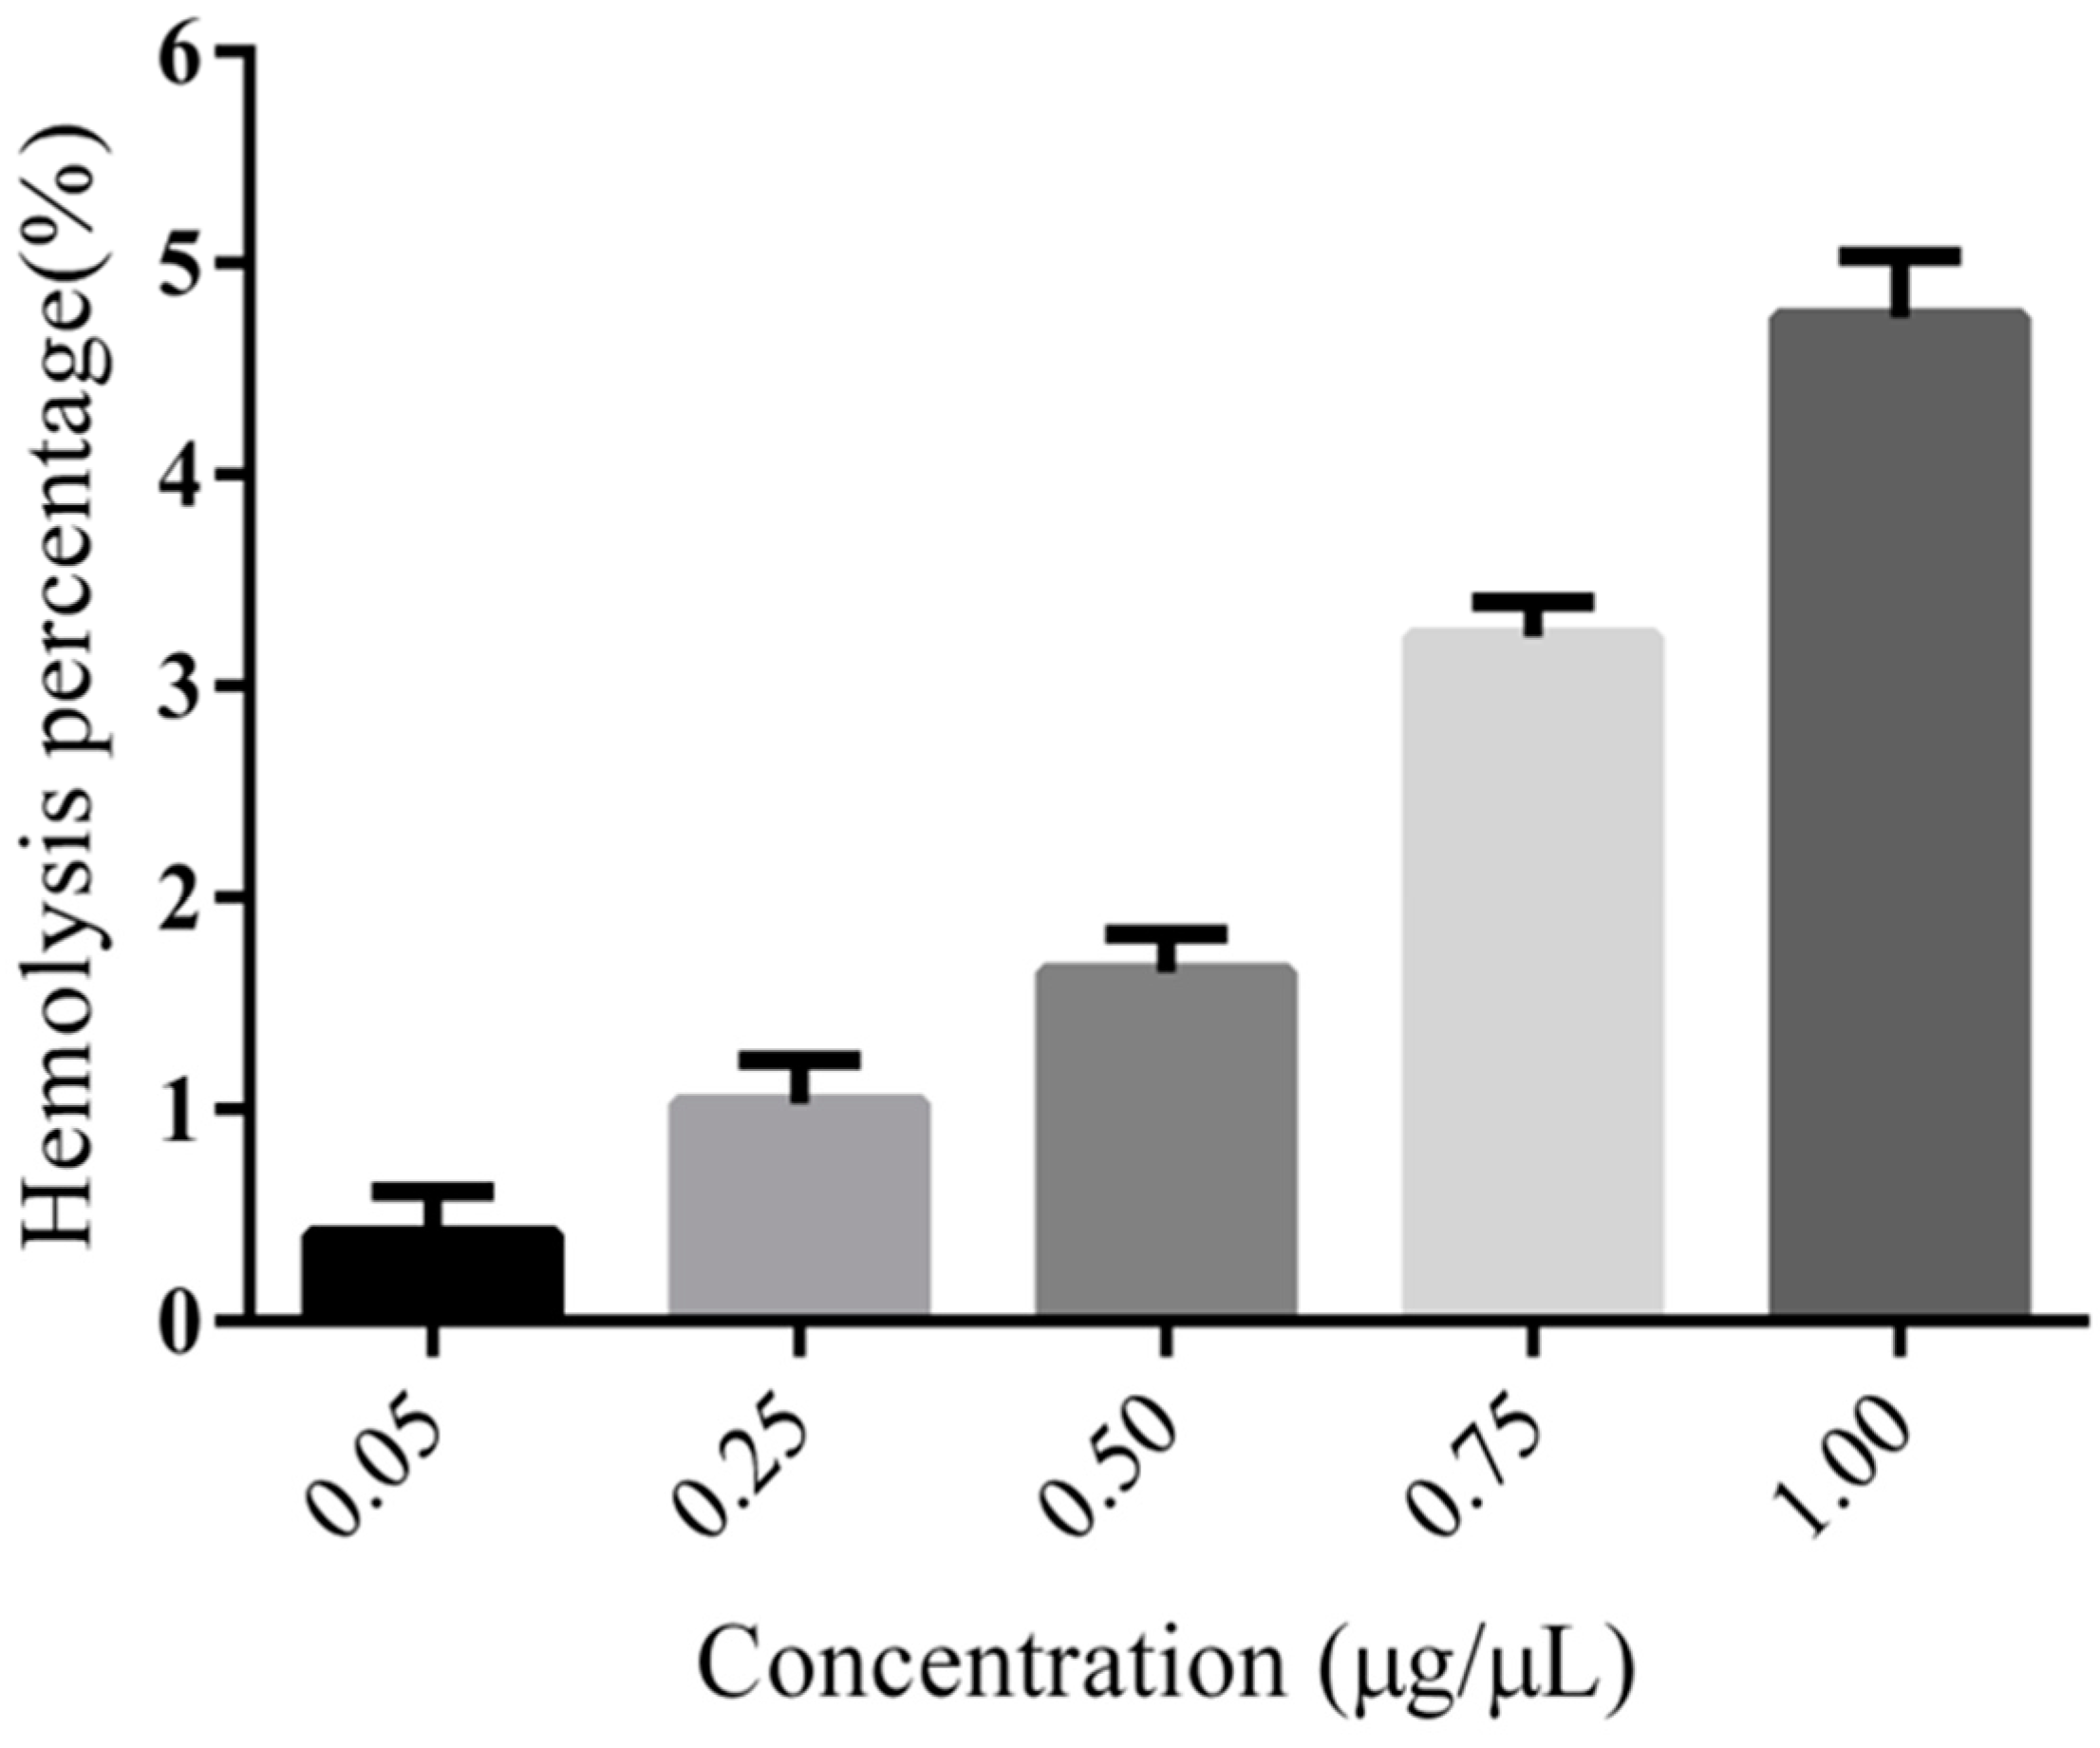

3.5. Hemolysis Assay of PEG-PLLA